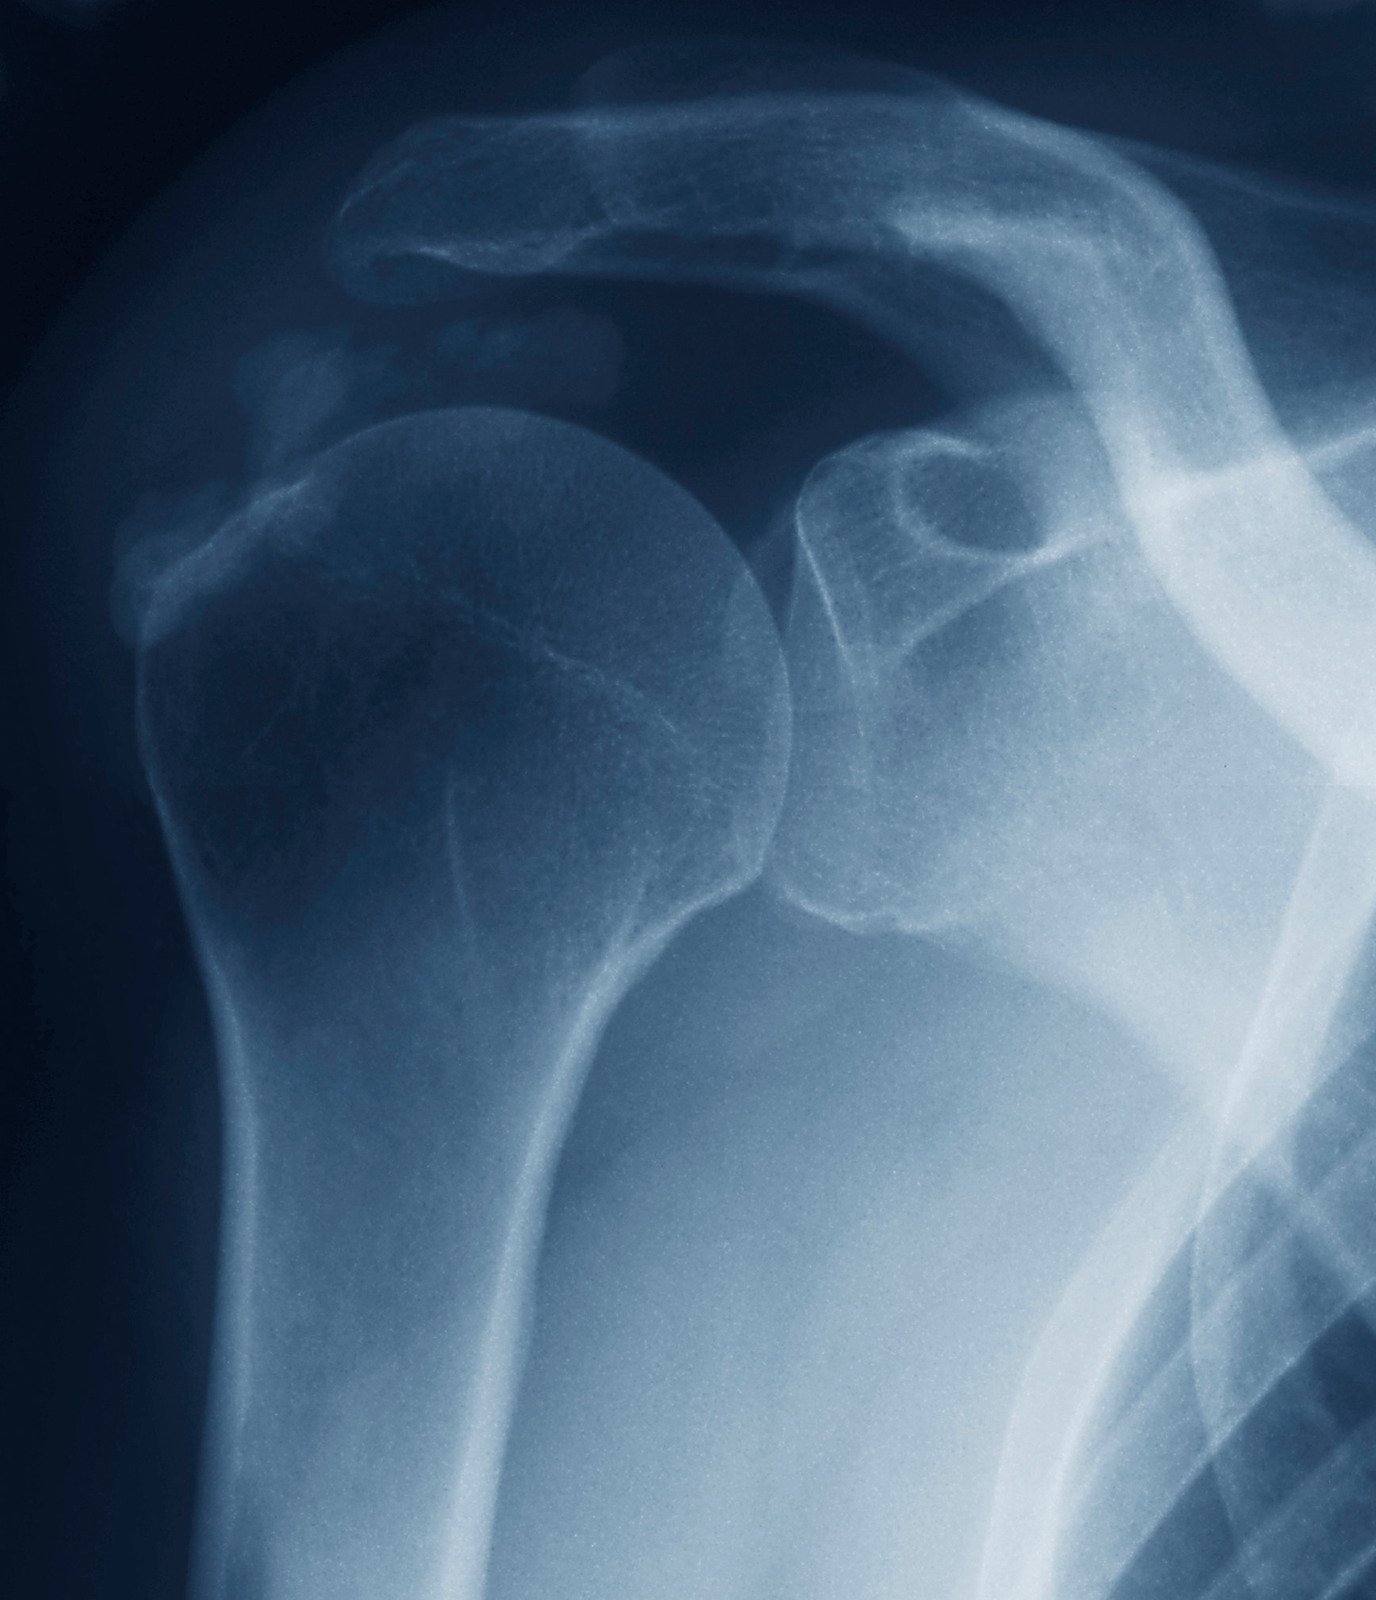

석회성 건염의 진단은 주로 증상, 신체 검사, 그리고 영상 검사(엑스레이, 초음파, MRI 등)를 통해 이루어집니다.

이러한 검사들은 석회화의 위치와 크기를 확인하는 데 도움이 됩니다.